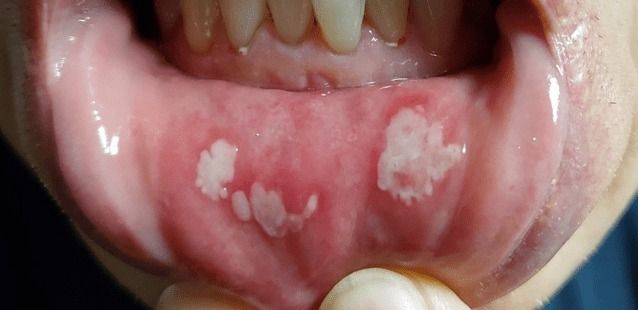

▲ 셀프 치아장치 사용 후 구강 점막에 궤양이 발생한 사례 [사진=대한치과의사협회]

한 사용자는 “양치와 식사조차 고통스럽다”며 장치 착용 후 치은부종과 궤양 사진을 공개하기도 했다. 또 다른 소비자는 장치 파편을 삼킬 뻔한 경험을 털어놓으며 “이갈이보다 더 큰 평생의 불안을 안게 됐다”고 호소했다.